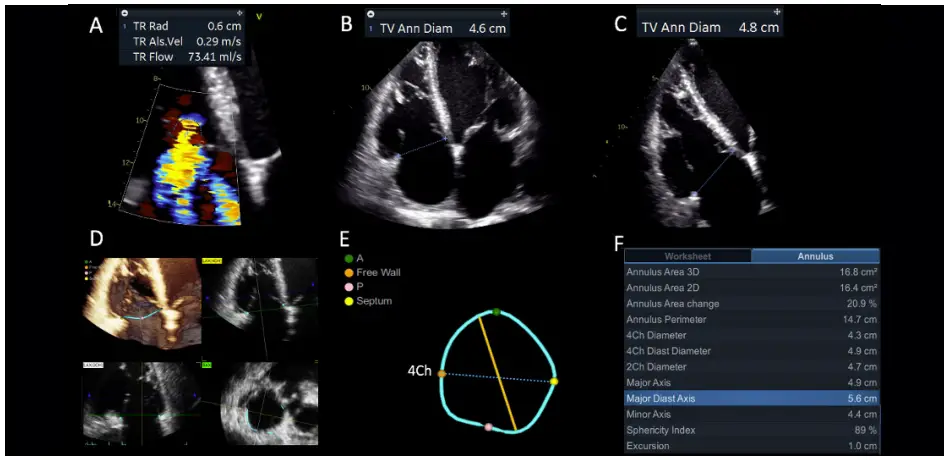

Figure 1. FTR in patient with pulmonary hypertension due to ischemic left-heart disease. A, PISA radius suggesting moderate FTR; B, TA diameter measured in 4-chamber view; C, TA diameter measured in RV-focused view; D, Quantification of TA geometry by 4D Auto TVQ tool; E, TA model in diastole showing the major axis (yellow line) with respect to the orientation of 4-chamber view plane (light blue dashed line); F, Quantitative semi-automated measurements of TA using 4D Auto TVQ tool showed that the largest diameter of the TA (Major Diast Axis) is 56 mm, significantly larger than any of the 2D diameters and also than the diameter measured in 4Ch by the tool (4Ch Diast Diameter 49 mm).

Figure 1. FTR in patient with pulmonary hypertension due to ischemic left-heart disease.